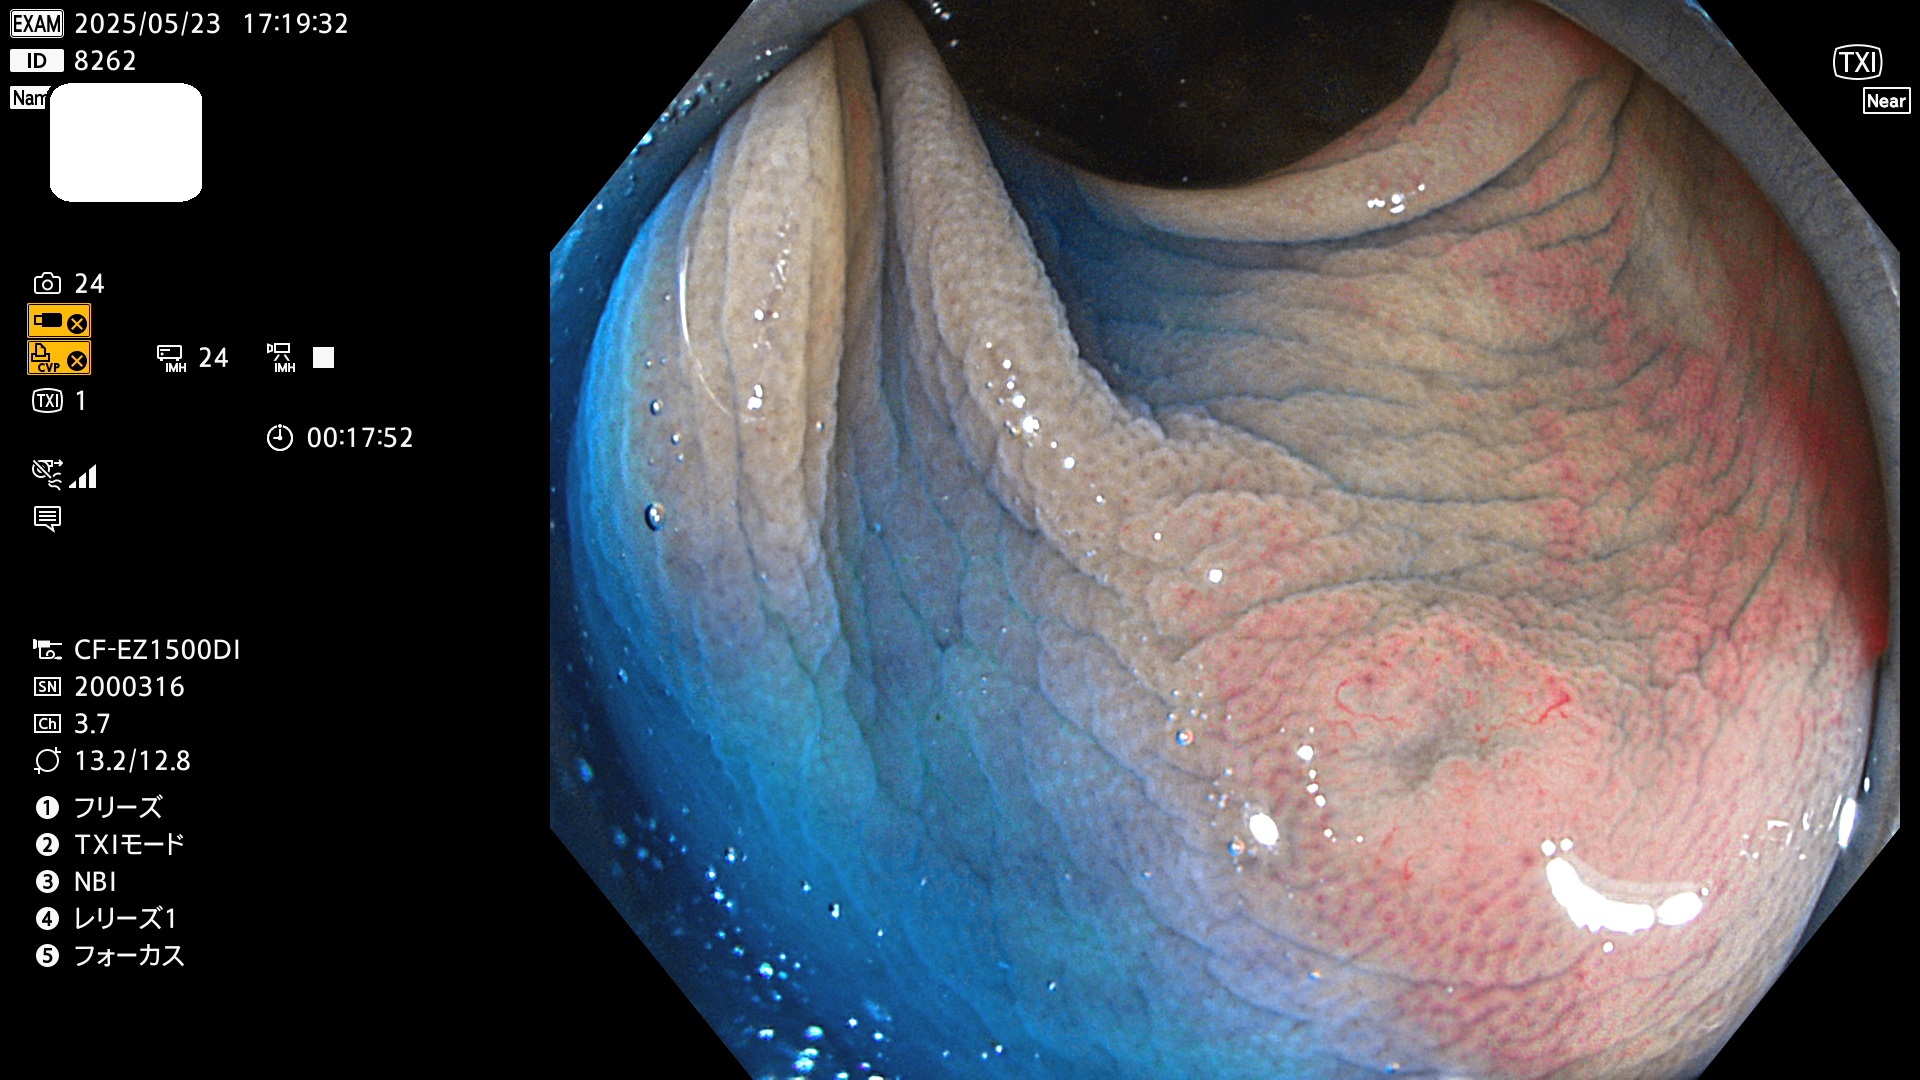

今週のUb、Uc型腺腫

完全に平坦な物をUb、陥凹している物をUcと呼びます。Ubは認識が困難で、Ucはびらん(炎症)と紛らわしいために見落とされやすく、「内視鏡後・大腸癌」の原因になります。

抽出の対象期間 2025年5月22日〜5月25日の4日間(48件の検査)10個 (10/48=21%)